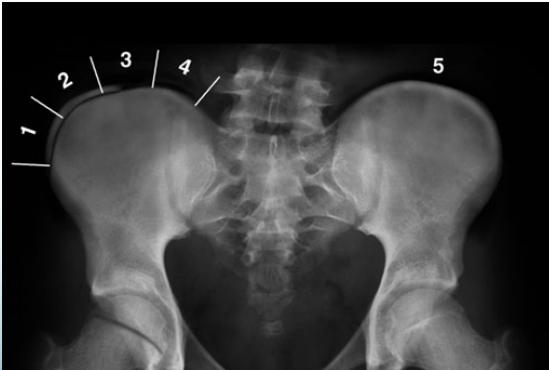

Risser’s Sign

- Measures potential for growth progression

- Ranges from 0 (no ossification) to 5 (complete bony fusion)

- Lower grade = Higher progression potential

Growth Assessment: Risser Grading

- Measures bony fusion of iliac apophysis

- Range: 0 (no ossification) to 5 (complete bony fusion)

- AP pelvis (Risser grade)